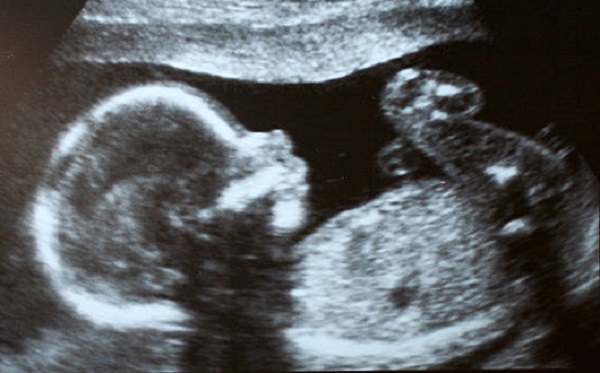

At 12 weeks of pregnancy, most women have the first major ultrasound. There should be three main ultrasound procedures over the nine months of pregnancy, spread out over a number of weeks.

In this first one, you should be able to see your baby’s movements for the first time. You should also get your first estimate of the expected date of delivery (EDD). This date might change as the pregnancy progresses. Only about 5% of pregnancies will meet this first estimate.

From the ultrasound, your doctor will be able to identify your baby’s hands and feet, the spine, aspects of brain development, the stomach full of fluid, and the bladder. To your untrained eye, all you will see is a cute baby floating in fluid.

This week’s ultrasound is also used to examine foetal viability. It will determine the thickness of the nuchal fold, an area behind the neck of the foetus that is considered a marker of genetic alterations like Down Syndrome and Turner Syndrome.

If the thickness is greater than three millimetres, which is the average that is considered normal in the 12th week of gestation, there may be a greater risk of Down Syndrome. If this is the case, your doctor may recommend performing an amniocentesis from the 16th week of pregnancy, or a corial biopsy (or chorionic villus sample) to confirm the diagnosis.